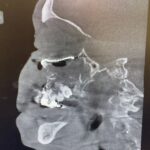

Our NJ team of Oral & Maxillofacial surgeons is trained to treat a variety of injuries to the mouth, face, and jaws. Our doctors maintain affiliations with NJ and NY hospitals and are often called to the emergency room to evaluate and treat traumatic facial injuries. Fractures (broken bones) can involve the lower jaw, upper jaw, cheekbones, eye socket, and combinations of these bones. Treatments for these injuries, such as jaw surgery are frequently managed in the operating room. Our doctors are board-certified and are on staff at Hackensack University Medical Center in NJ as well as Columbia University Medical Center in NY. We can manage and treat your injuries at any of these hospitals.